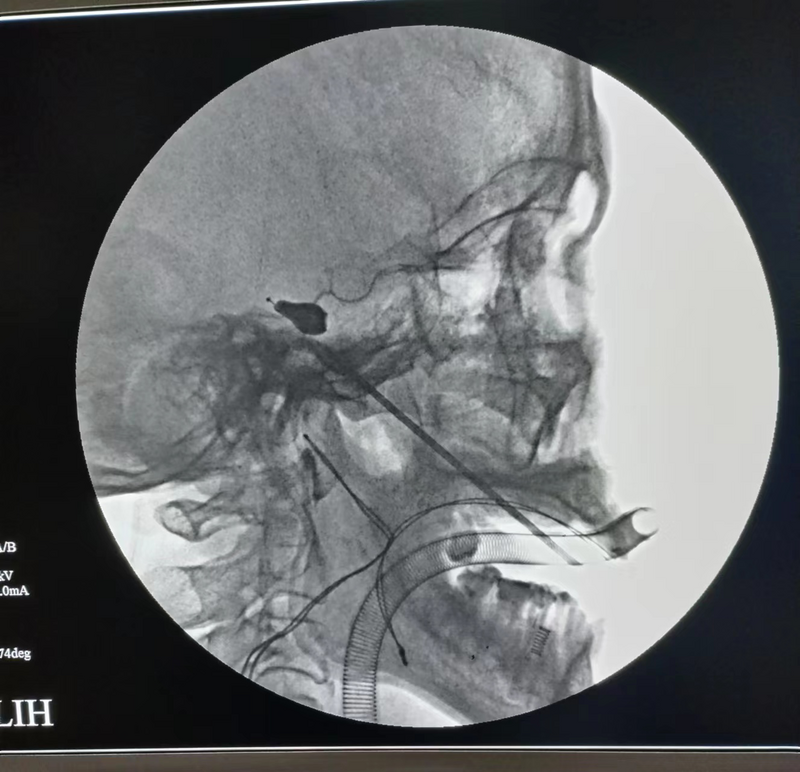

三叉神經(jīng)半月節(jié)球囊壓迫術(shù)(PBC),是指在影像引導(dǎo)下通過(guò)“微球囊”對(duì)半月節(jié)進(jìn)行短暫壓迫,從而阻斷痛覺神經(jīng)傳導(dǎo),最終達(dá)到祛除面痛的治療效果。與開顱手術(shù)相比,球囊壓迫術(shù)創(chuàng)傷僅有面部一個(gè)針眼,創(chuàng)傷較小,術(shù)后恢復(fù)快,同時(shí)有著手術(shù)時(shí)間短、風(fēng)險(xiǎn)低、費(fèi)用低、療效確切等優(yōu)點(diǎn)。